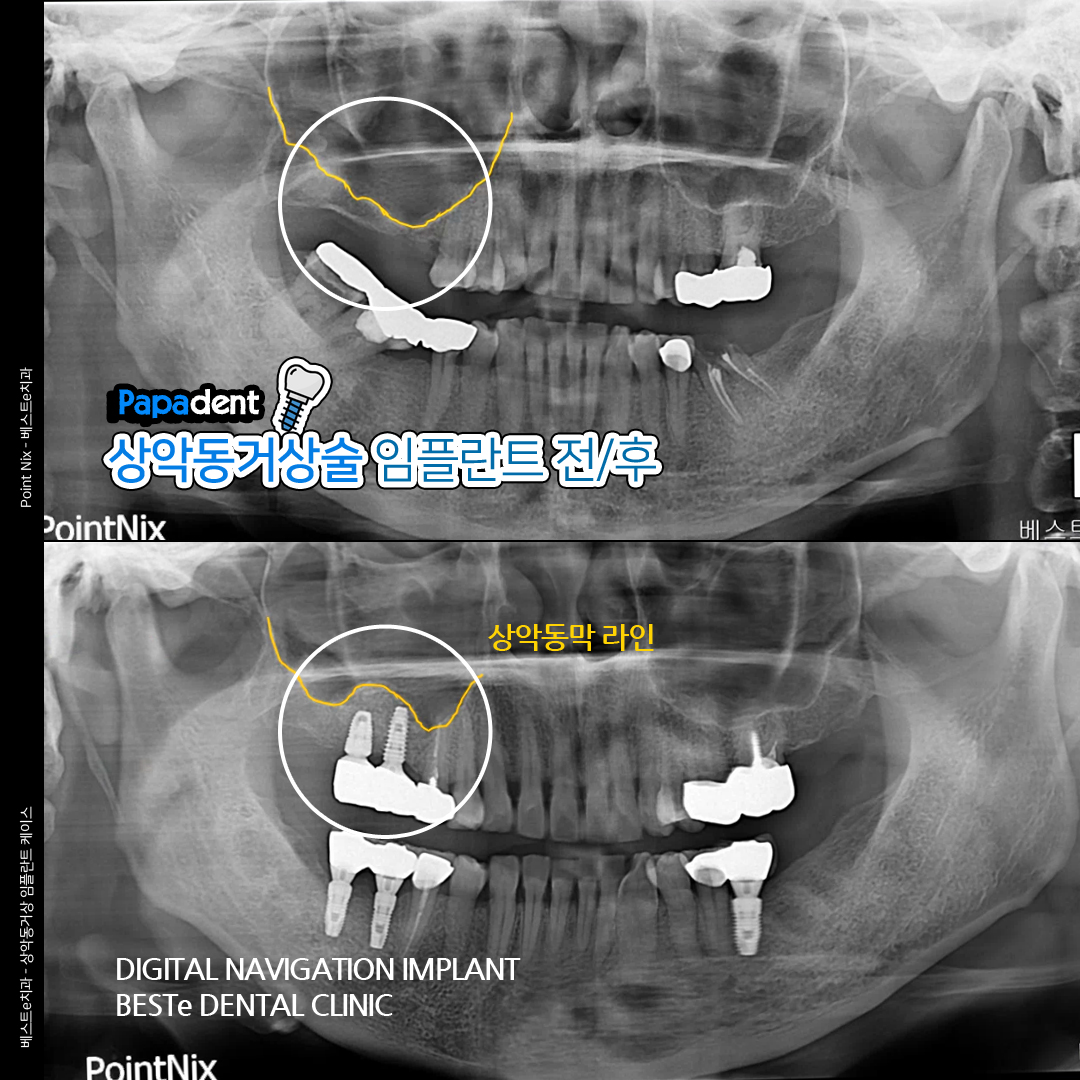

환자 건강을 최우선으로 생각하는 베스트e치과의원! 연세대 치의학박사 원장님이 전문적이고 양심적인 진료를 약속한다. 수준 높은 디지털 의료 장비로 안전하고 정확하게 진료하는 것이 장점!

디지털 임플란트, 심미 치료, 충치 치료, 치아 미백, 턱관절 치료까지! 다양한 진료를 한 곳에서 받을 수 있어 편리하다. 쾌적한 환경에 친절한 서비스는 덤!